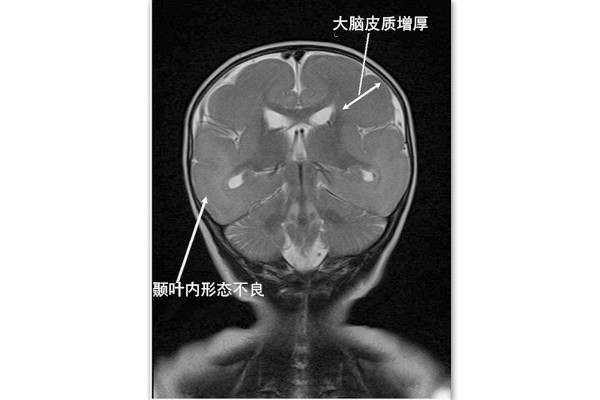

Miller-Dieker综合征(MDS)又叫无脑综合征,是一种以脑部CT显示为大脑无褶皱和沟槽为主要特征的罕见疾病,其发病率约为1/250000。正常情况下,大脑皮层在影像学观察下,是多层的褶皱和沟槽构成,而无脑综合征患者的大脑褶皱和沟槽较少,就像一个橄榄球一样异常光滑。这种大脑畸形会导致严重的智力障碍、发育迟缓、癫痫、异常的肌肉僵硬(痉挛)、肌张力减弱和进食困难。这些症状会在儿童期间进一步加重,造成呼吸肌痉挛,从而导致呼吸衰竭而死亡。

Miller-Dieker综合征(MDS)的典型特征是脑部CT显示为大脑无褶皱和沟槽,大脑皮层异常光滑。其余相关临床症状还有: